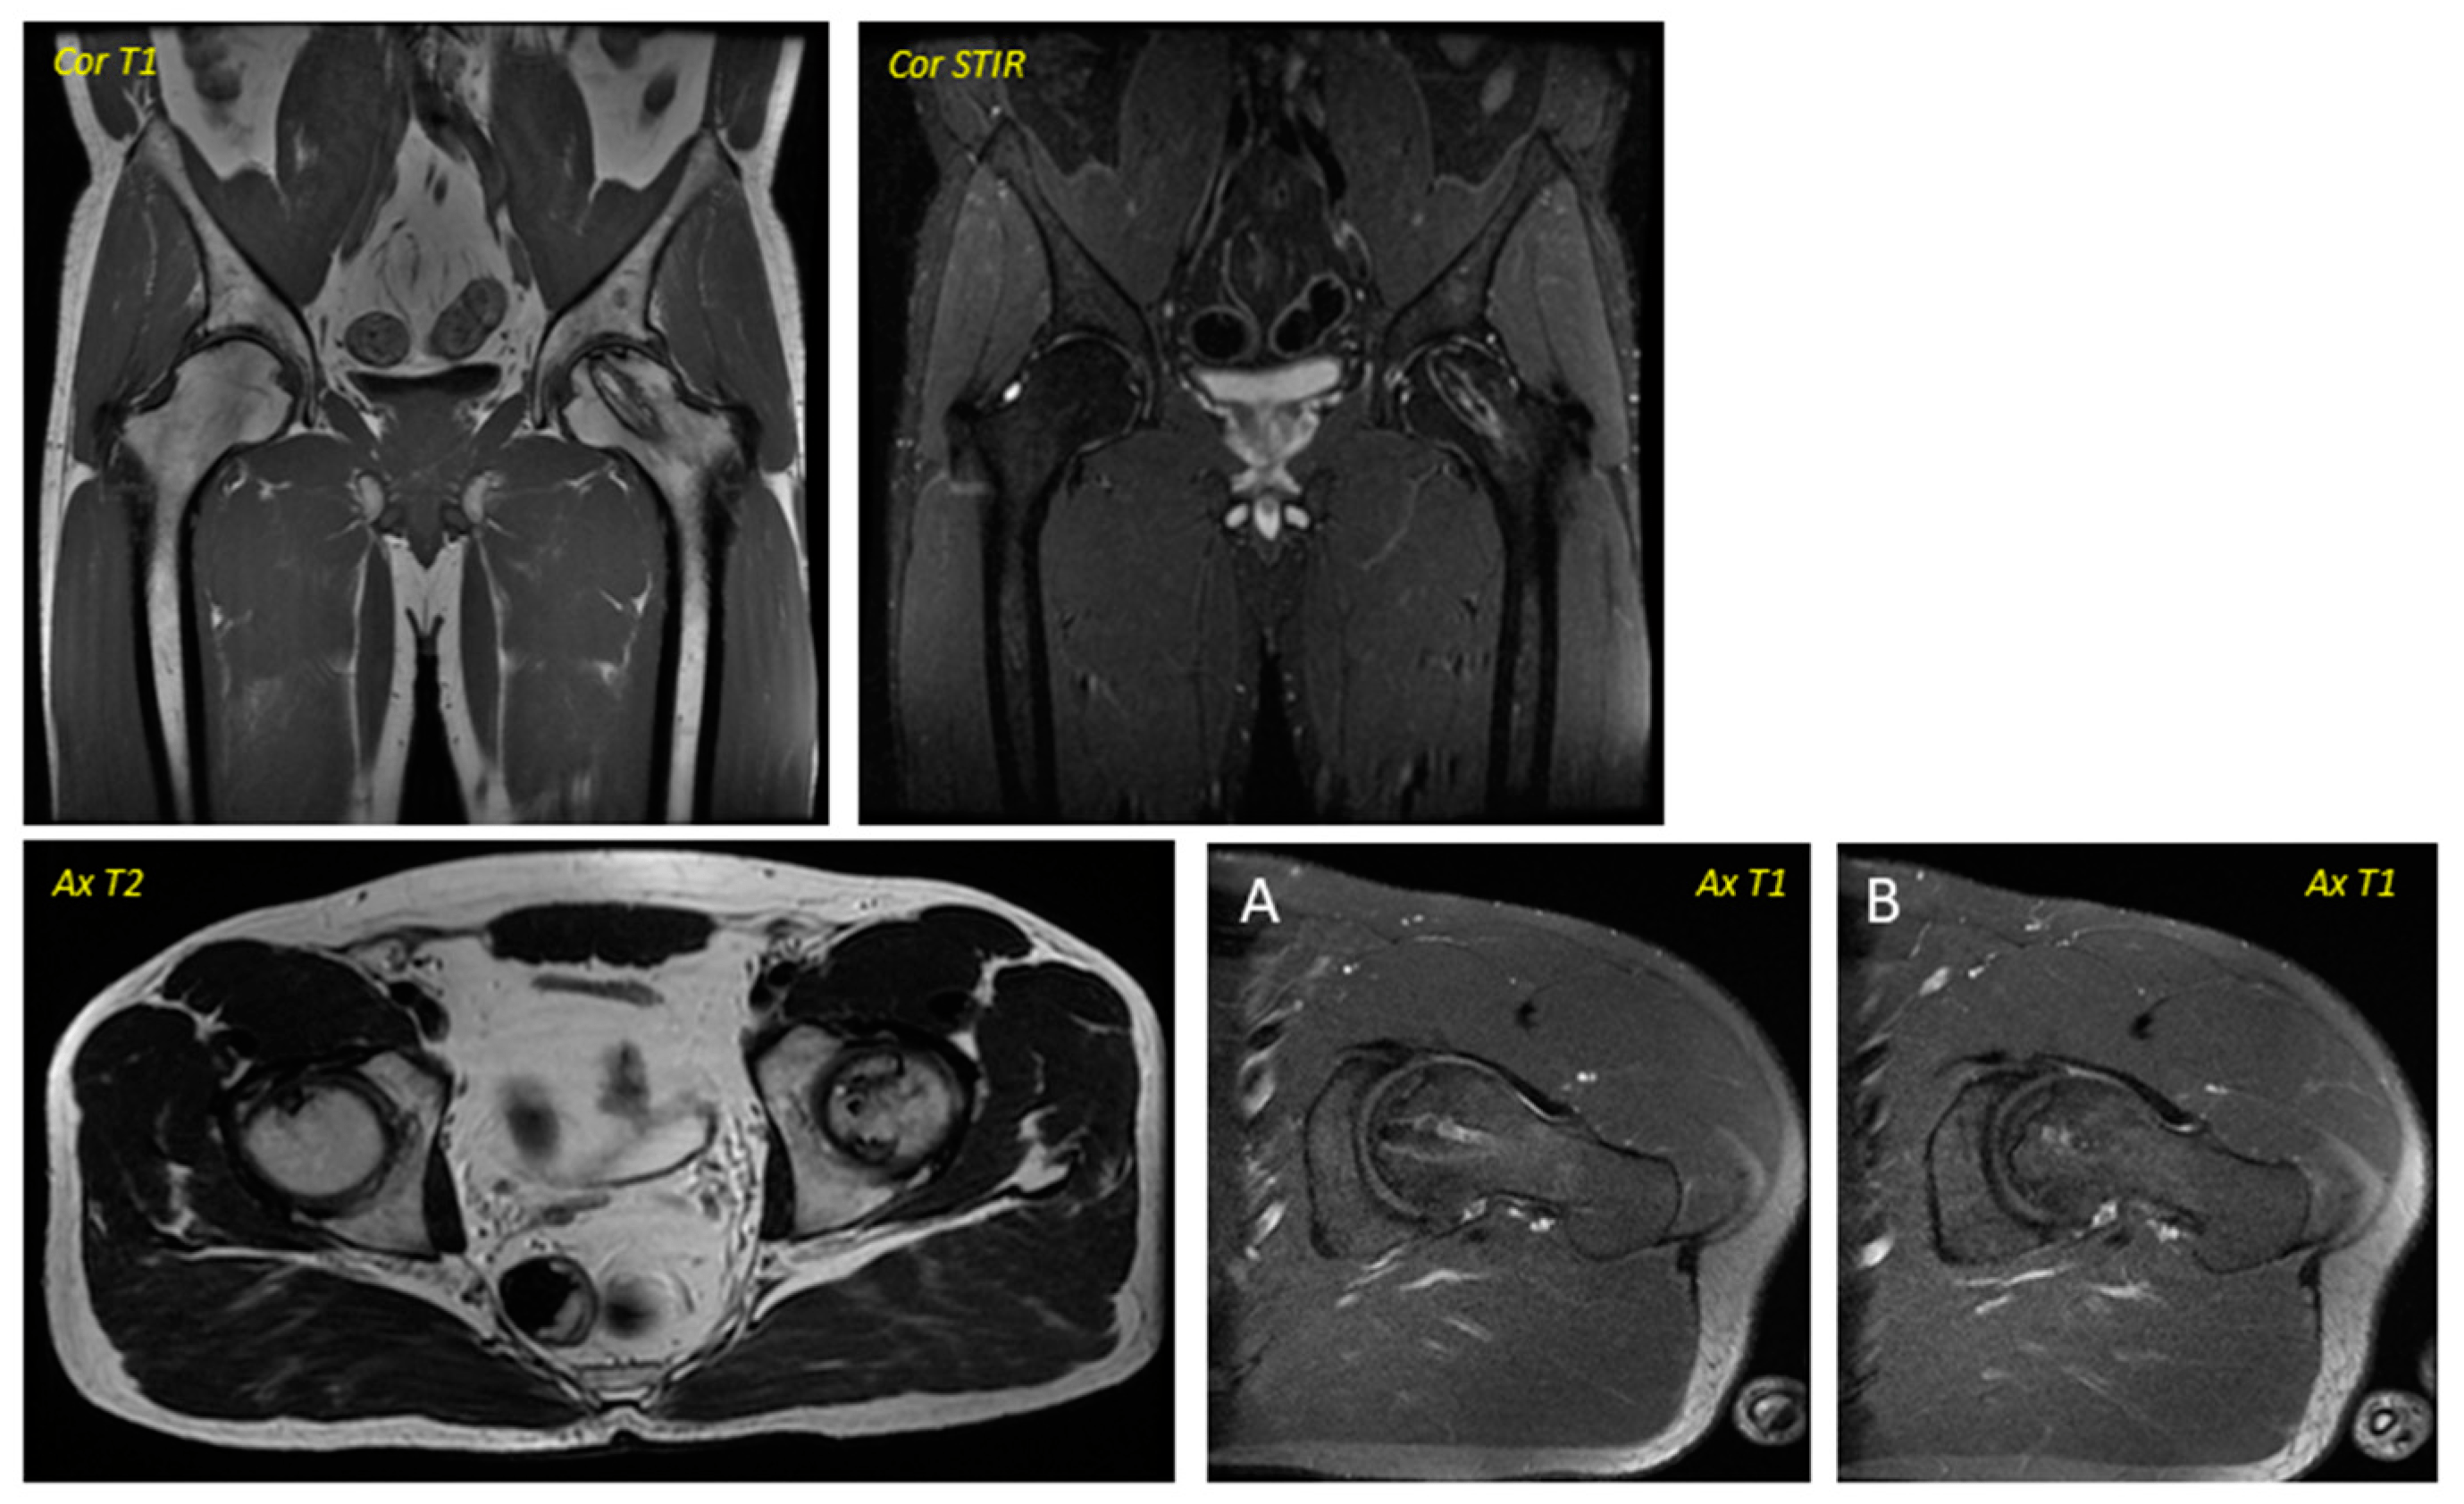

關于影像學研究,在12個月的隨訪期間,在影像學演變中觀察到了一些發現(圖1和圖2)。

首先,方向的變化從第六個月開始出現在所有病例中,而在早期階段并不明顯。其次,62.5%的患者 ( n=5) 在手術后的第一年內實現了影像穩定。第三,兩名患者 (25%) 出現壞死區進展,而一名 (12.5%) 患者出現明顯的再骨化跡象。盡管觀察到描述性差異,但后一個參數的p值在統計學上并不顯著。